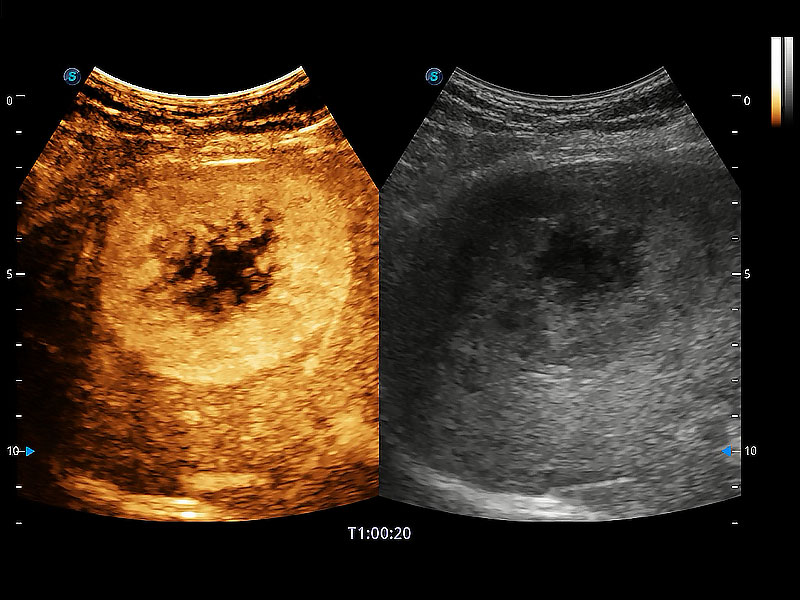

(犬)肝脏

• 全面的造影成像

非线性融合造影成像充分利用谐波和基波信号,为难以观察的血流进行增强显像。可用于线阵、凸阵、微凸阵、相控阵探头。